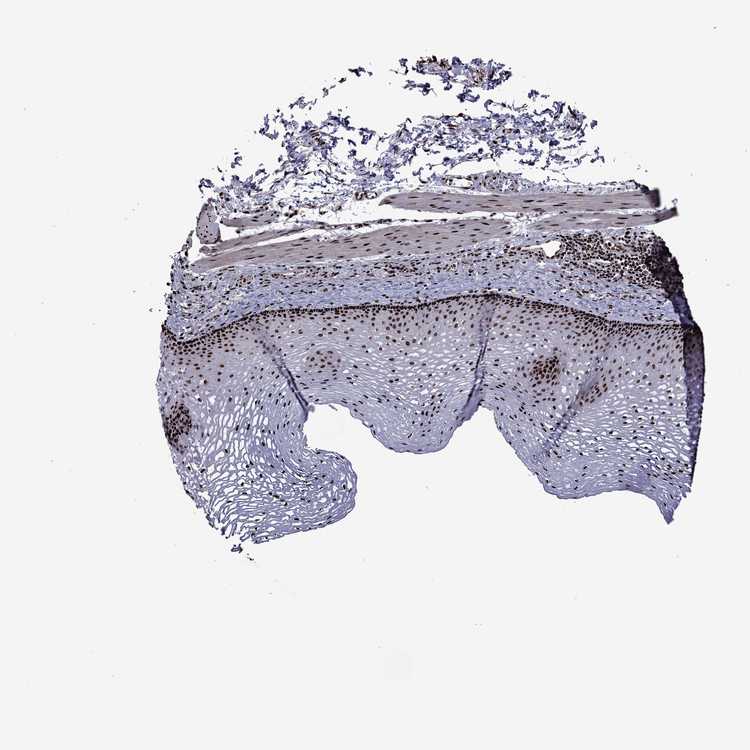

ESOPHAGUS - Antibody stainingi

Antibody staining in the annotated cell types in the current human tissue is reported as not detected, low, medium, or high, based on conventional immunohistochemistry profiling in selected tissues. This score is based on the combination of the staining intensity and fraction of stained cells.

Each image is clickable and will lead to virtual microscopy that enables deeper exploration of all samples and also displays staining intensity scores, fraction scores and subcellular localization as well as patient and tissue information for each sample.

Antibody HPA028516Antibody HPA073571

Squamous epithelial cells HighHigh